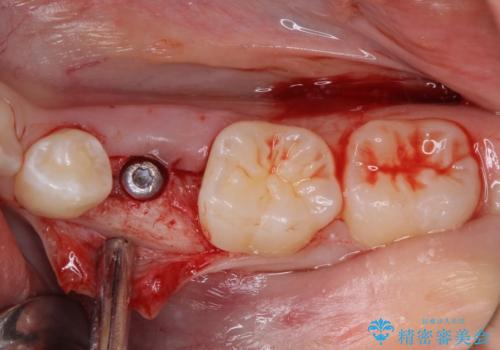

左下には後続永久歯の欠損した乳歯が残存しており、叢生を相まって咬合関係が乱れていました。

乳歯は抜歯し、インビザラインにて矯正治療を行いながら、並行してインプラントによる補綴治療を行うこととしました。

矯正治療が終わるタイミングに合わせてインプラントの埋入を行っていたので、矯正治療を終了すると同時にセラミック補綴治療を行えました。